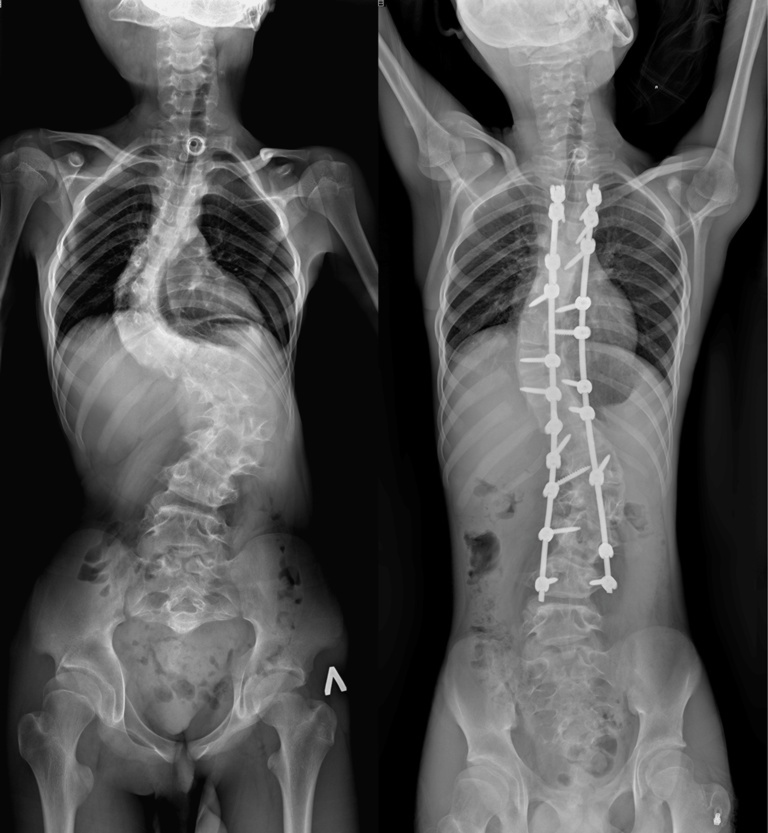

Врачи отделения травматологии и ортопедии РДКБ РНИМУ им. Н.И. Пирогова Минздрава России провели успешную операцию по коррекции кифосколиоза у пациента с синдромом Протея. Хирургическое вмешательство длилось более семи часов и было технически сложным: кифотическая деформация грудного отдела позвоночника составляла более 110 градусов, а комбинированная сколиотическая — по 90 градусов в грудном и поясничном отделах. Благодаря слаженной работе опытной команде хирургов удалось добиться существенной коррекции и обеспечить пациенту достойное качество жизни в будущем. По словам врачей, мальчик даже сможет заниматься своим любимым делом — кататься на велосипеде.

«К нам он поступил с уже существенным искривлением позвоночника, — отмечает Андрей Андреевич. — Кифотическая деформация грудного отдела составляла более 100 градусов, а сколиотическая — более 90 градусов в грудном и поясничном отделах. Отмечались нарушения походки, а совокупность этих и других проблем пациента, связанных с основным диагнозом, сильно влияла на его качество жизни».

После операции Мурат быстро активизировался и восстанавливался. Хирургам удалось добиться невероятных результатов в коррекции: угол кифотической деформации был снижен до 60 градусов (практически вдвое), а сколиотических — до 40-50 градусов, обеспечен удовлетворительный баланс позвоночника в сагиттальной и фронтальной плоскостях.